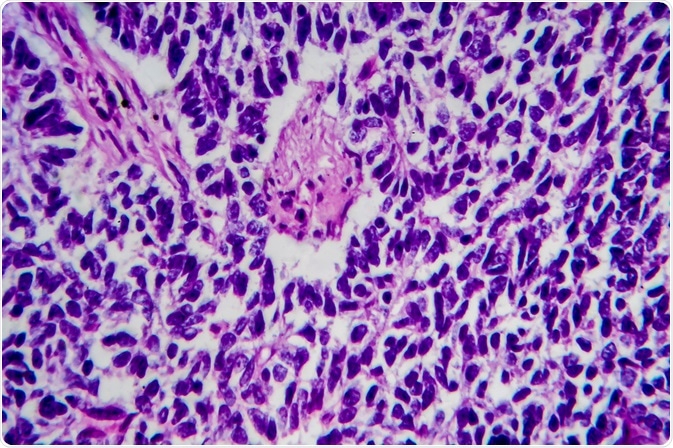

wilms tumorImage Credit: Kateryna Kon / Shutterstock.com

One of the most important categorizations that can help to estimate prognosis is the histology of the cancer cells, based on the microscopic appearance.

Cells with favorable histology account for the majority of Wilms tumor cases and involve cancer cells that display abnormal characteristics but do not have large defects in the genetic DNA. This type is associated with a positive prognosis, often more than 90% depending on the progression of the tumor.

Unfavorable histology is marked by cancer cells with wide variations in appearance with the nucleus of the cell usually appearing swollen and distorted. This effect is known as anaplasia and is more difficult to treat and hence associated with a poorer prognosis.